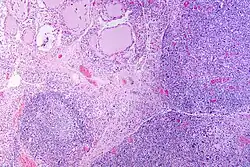

A micrograph of the thyroid of someone with Hashimoto's thyroiditis

Marked lymphocytic infiltration (purple areas) of the thyroid gland in a patient with chronic autoimmune thyroiditis

High powered magnification showing lymphocytic infiltration of the thyroid gland in autoimmune thyroiditis

Gross pathology of a thyroid with autoimmune thyroiditis may show a symmetrically enlarged thyroid.[5] It is often paler in color, in comparison to normal thyroid tissue, which is reddish-brown.[5]

Microscopic examination (histology) will show lymphocytes (including plasma B-cells) diffusely infiltrating the parenchyma.[55] The lymphocytes are predominately T-lymphocytes with a representation of both CD4+ and CD8+ cells.[5] The plasma cells are polyclonal, with present germinal centers resembling the structure of a lymph node[5] (also called secondary lymphoid follicles, not to be confused with the normally present colloid-filled follicles that constitute the thyroid).[55]

In late stages of the disease, the thyroid may be atrophic.[10] Colloid-filled follicles shrink, and the cuboidal cells that usually line the follicles become Hürthle cells.[5] Fibrous tissue may be found throughout the affected thyroid as well.[5] Severe thyroid atrophy presents often with denser fibrotic bands of collagen that remain within the confines of the thyroid capsule.[55]

Generally, pathological findings of the thyroid are related to the amount of remaining thyroid function — the more infiltration and fibrosis, the less likely a patient will have normal thyroid function.[5] A rare but serious complication is thyroid lymphoma, generally the B-cell type, non-Hodgkin lymphoma.[24]